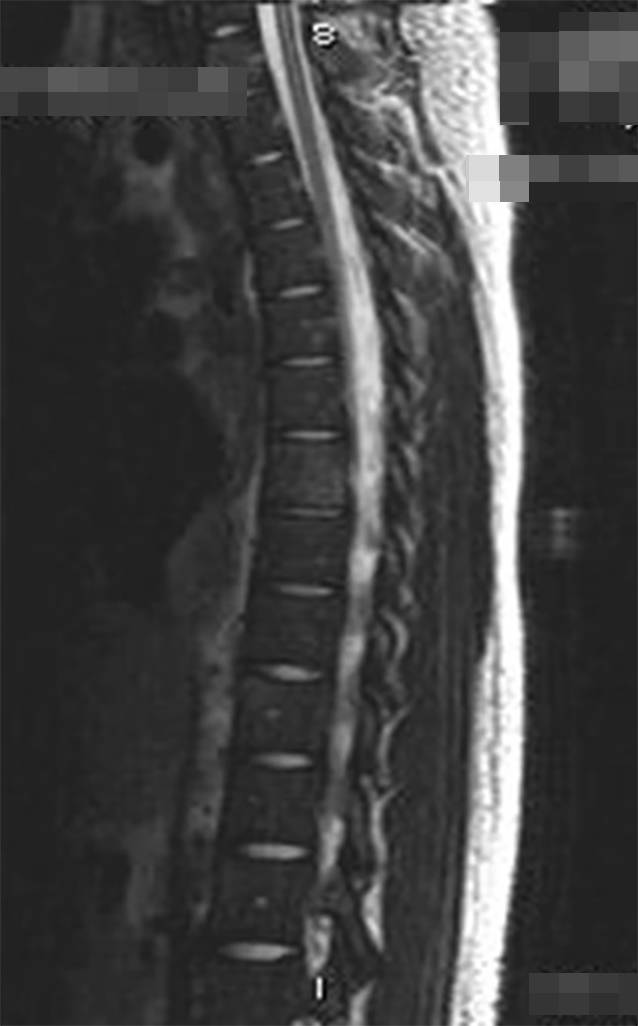

A 14-year-old African American female presented with a 3-month history of shortness of breath, fever, night sweats, and 13.6 kg weight loss. Physical examination showed a superficial forehead skin lesion, and there was no evidence of hepatosplenomegaly (Fig. 1). Computed tomography (CT) and magnetic resonance imaging (MRI) scans revealed diffuse bilateral hilar and mediastinal lymphadenopathy, including multiple infiltrative lesions that involved the thoracic and lumbar vertebral bodies and sacrum (Fig. 2).

Fig. 2

MRI revealing multiple infiltrative lesions involving thoracic and lumbar vertebral bodies

These findings were clinically and radiologically suspicious for lymphoma. The patient underwent bone marrow biopsy to rule out lymphoma, a solid tumor, or an infection with marrow involvement. The bone marrow biopsy was significant for a slightly left-shifted myeloid hyperplasia, mild megakaryocytic hyperplasia, and mild marrow eosinophilia. Significantly, thick-walled non-budding spherules with a granulomatous giant cell reaction were present within the bone marrow trephine core section and stained positively for periodic acid–Schiff (PAS) and Grocott’s methenamine silver (GMS; Figs. 3, 4, 5 and 6). In addition, fungal hyphae with arthrospores were detected in the patient’s blood and bronchial alveolar lavage cultures, and she was conclusively diagnosed with disseminated coccidioidomycosis.